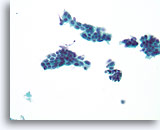

Lobulair carcinoom, Borst FNA, celblok.

Lobulaire carcinoomcellen lijken in het stromaweefsel te zijn ingebed, zodat de indruk wordt gewekt van hypercellulariteit. Dit kan de reden zijn waarom cytologische preparaten van een lobulair carcinoom vaak weinig maligne cellen tonen.

20X

Lobulair carcinoom, Borst FNA, celblok.

Lobulaire carcinoomcellen lijken in het stromaweefsel te zijn ingebed, zodat de indruk wordt gewekt van hypercellulariteit. Dit kan de reden zijn waarom cytologische preparaten van een lobulair carcinoom vaak weinig maligne cellen tonen.

20X

Lobulair carcinoom, Borst FNA, celblok.

Een enkele rij minimaal atypische spaarzame cellen die op en in de stromale fragmenten vastzitten, kan worden waargenomen. Let op de kenmerkende targetoïde intracytoplasmische vacuolen van lobulaire neoplasie.

40X

Lobulair carcinoom, Borst FNA, celblok.

Een enkele rij minimaal atypische spaarzame cellen die op en in de stromale fragmenten vastzitten, kan worden waargenomen. Let op de kenmerkende targetoïde intracytoplasmische vacuolen van lobulaire neoplasie.

40X